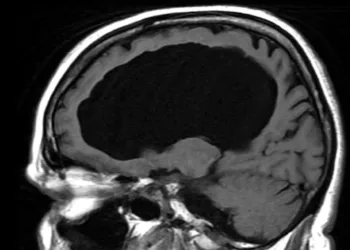

Când un bărbat a ajuns la un spital din Franța plângându-se că are o durere de picior, în 2007, Dr....